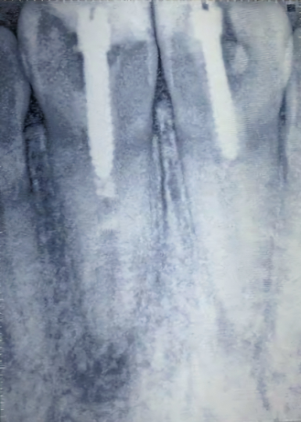

Evaluación radiográfica

La radiografía periapical preoperatoria revela tornillos tipo Dentatus en ambos incisivos centrales sin evidencia de obturación radicular y presencia de procesos periapicales (Fig.3).

Fig. 3 Rx Pre op